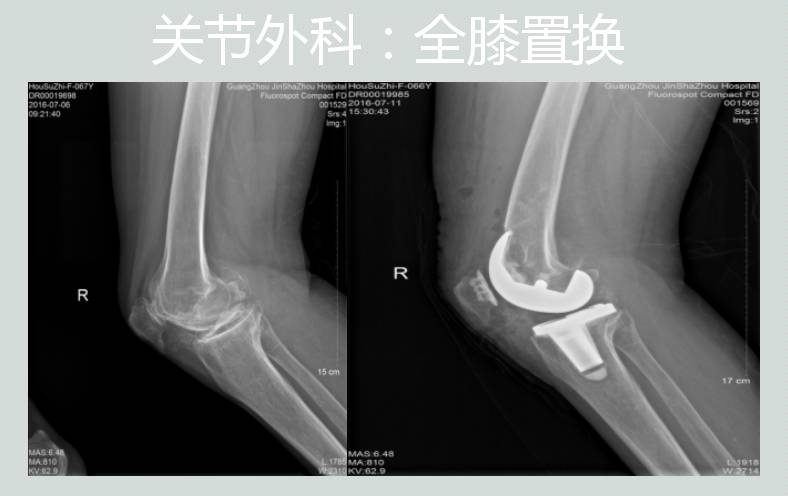

各种关节疾病的诊断与外科治疗:髋、膝关节的人工关节置换及翻修手术、骨关节炎、类风湿性关节炎、强直性脊柱炎的髋膝关节病变的外科治疗、股骨头缺血性坏死的外科治疗、股骨颈骨折和股骨粗隆间骨折的外科治疗、先天性髋关节脱位的诊断与治疗,各种小儿四肢骨关节病变的治疗、关节镜的检查与微创治疗等。